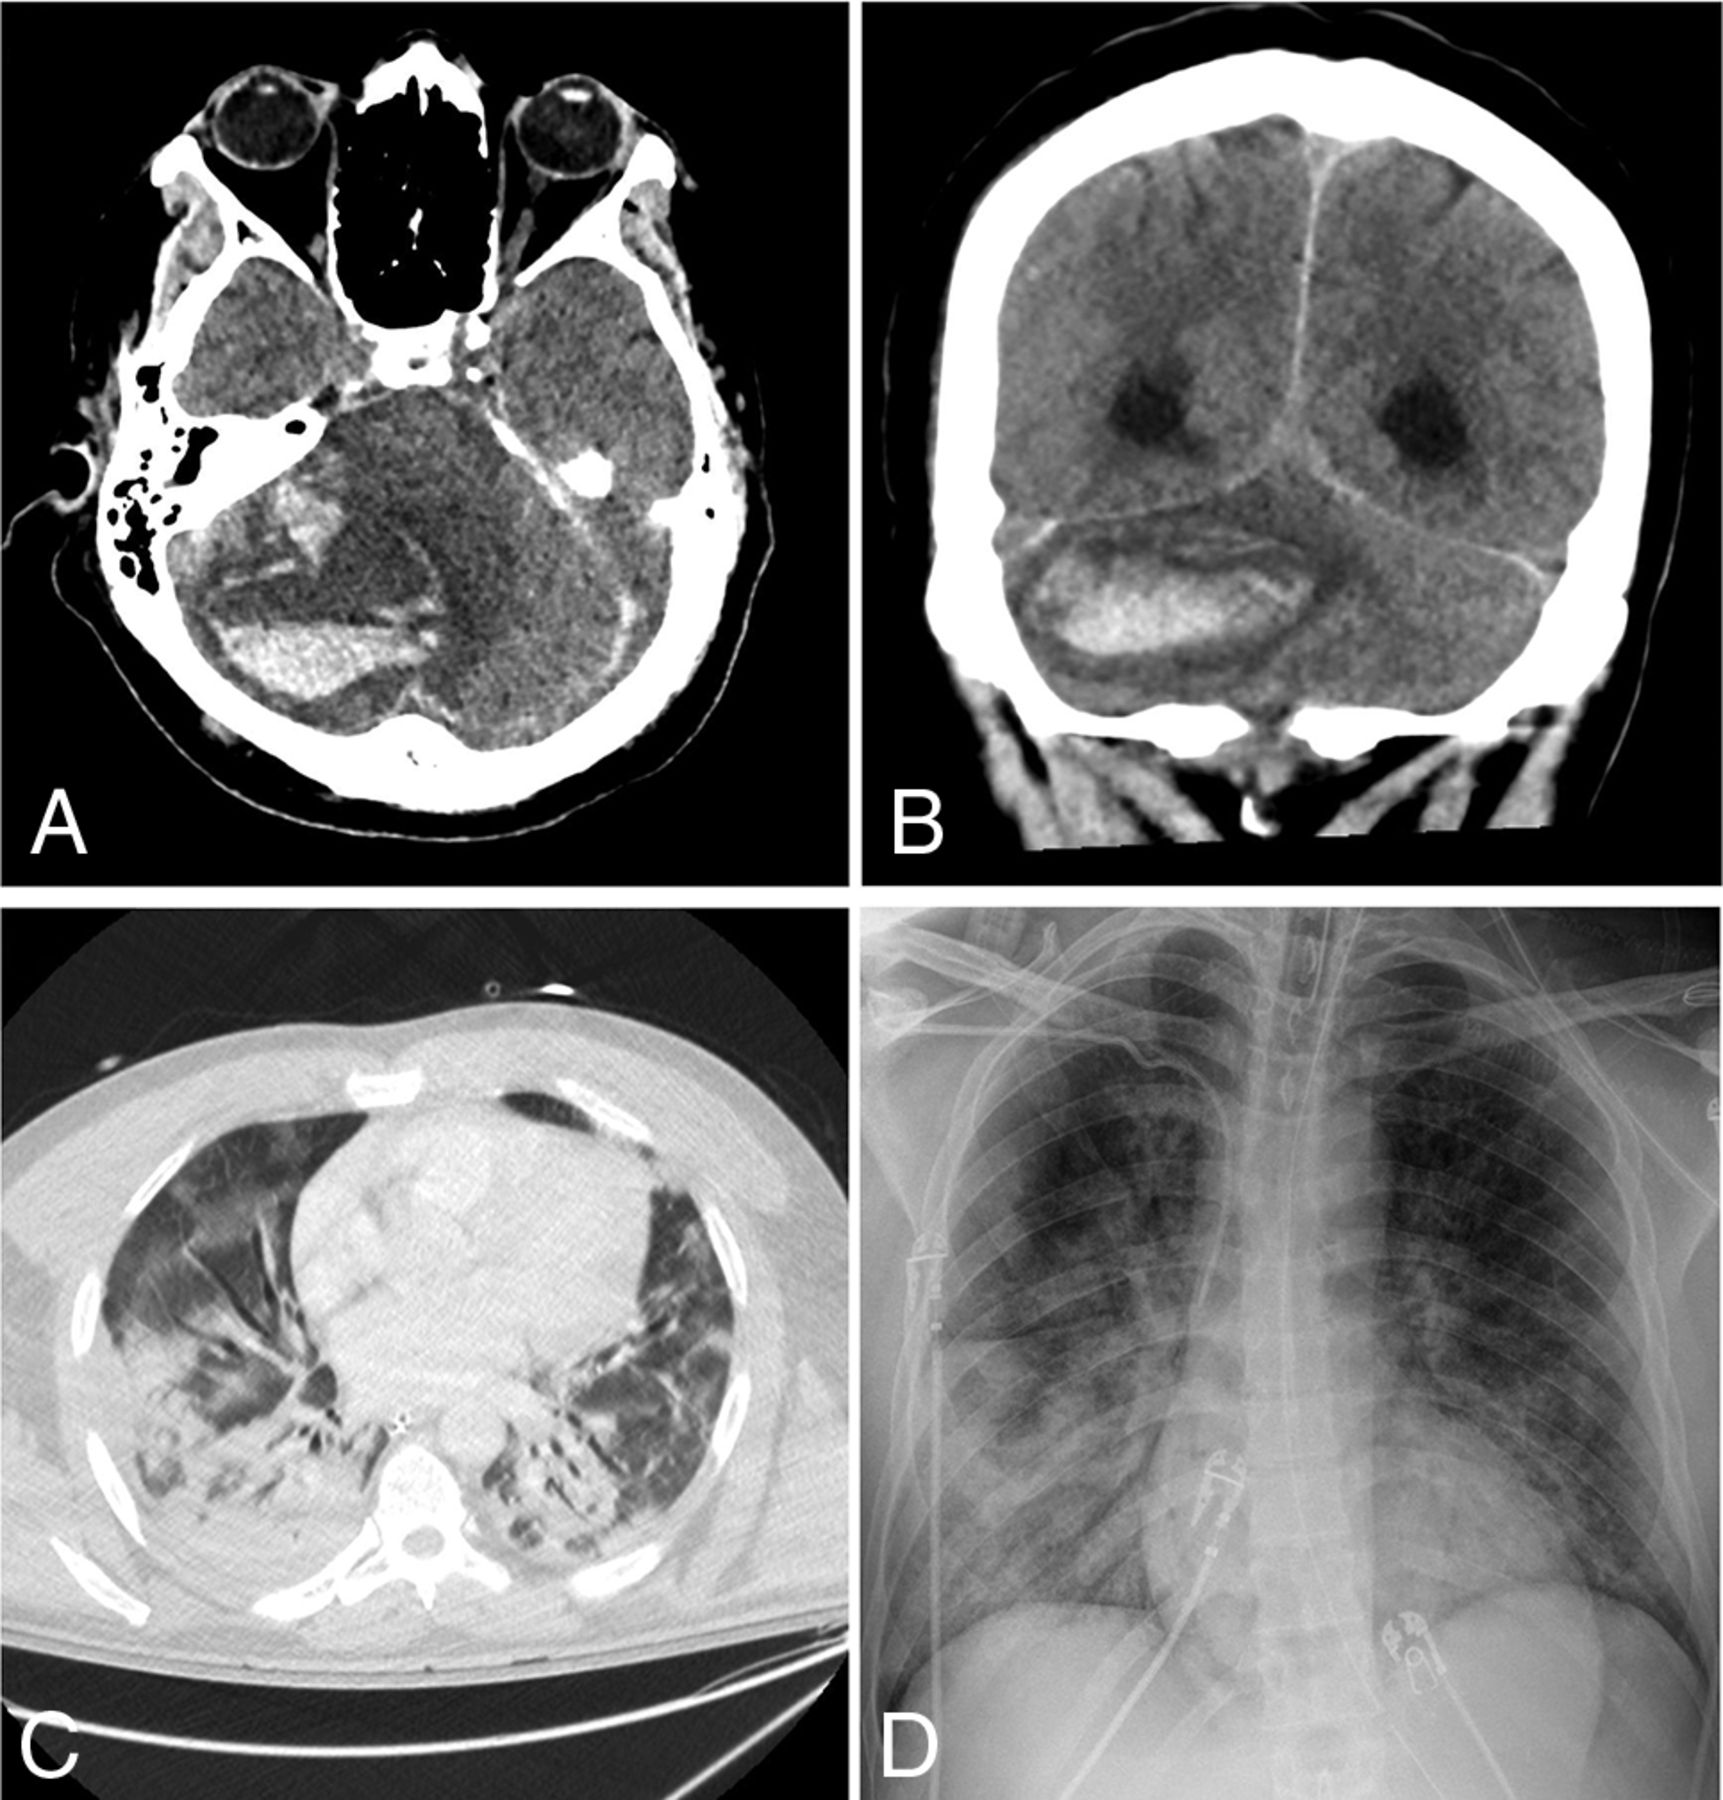

Of the 24 patients with acute neuroimaging findings, 7 patients were found to have intracranial hemorrhage (Fig 1), 7 patients were found to have acute infarction (Fig 2), 6 patients were found to have leukoencephalopathy (Fig 3), 3 patients had intracranial hemorrhage and infarction, and 1 patient had intracranial hemorrhage, infarction, and leukoencephalopathy (Table 2). Sixty-nine patients did not have acute neuroimaging findings (Fig 4). There was no significant difference (P = .225) between the distribution of Radiological Society of North America categories of chest CT findings between patients without acute neuroimaging findings (n = 66) and those with acute neuroimaging findings (n = 14), with the “typical” category being the most prevalent in both groups (Table 2).21

An 85-year-old man presented with increasing shortness of breath. Non-contrast-enhanced axial CT of the head demonstrates multiple new foci of hypoattenuation within the bilateral frontal corona radiata (arrows on A) and left centrum semiovale (arrow on B), in keeping with acute infarcts. C, Chest CT of the patient shows diffuse bilateral, right greater-than-left, predominantly consolidation and ground-glass opacities as well as bilateral pleural effusions. The CCS score was calculated as 13. D, Portable chest radiograph demonstrates bilateral patchy opacities with a PXS score of 10.6.